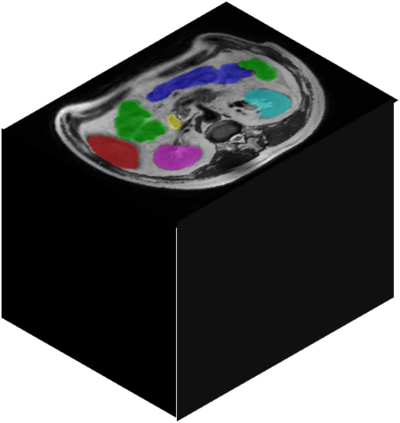

Vision transformers, with their ability to more efficiently model long-range context, have demonstrated impressive accuracy gains in several computer vision and medical image analysis tasks including segmentation. However, such methods need large labeled datasets for training, which is hard to obtain for medical image analysis. Self-supervised learning (SSL) has demonstrated success in medical image segmentation using convolutional networks. In this work, we developed a \underline{s}elf-distillation learning with \underline{m}asked \underline{i}mage modeling method to perform SSL for vision \underline{t}ransformers (SMIT) applied to 3D multi-organ segmentation from CT and MRI. Our contribution is a dense pixel-wise regression within masked patches called masked image prediction, which we combined with masked patch token distillation as pretext task to pre-train vision transformers. We show our approach is more accurate and requires fewer fine tuning datasets than other pretext tasks. Unlike prior medical image methods, which typically used image sets arising from disease sites and imaging modalities corresponding to the target tasks, we used 3,643 CT scans (602,708 images) arising from head and neck, lung, and kidney cancers as well as COVID-19 for pre-training and applied it to abdominal organs segmentation from MRI pancreatic cancer patients as well as publicly available 13 different abdominal organs segmentation from CT. Our method showed clear accuracy improvement (average DSC of 0.875 from MRI and 0.878 from CT) with reduced requirement for fine-tuning datasets over commonly used pretext tasks. Extensive comparisons against multiple current SSL methods were done. Code will be made available upon acceptance for publication.